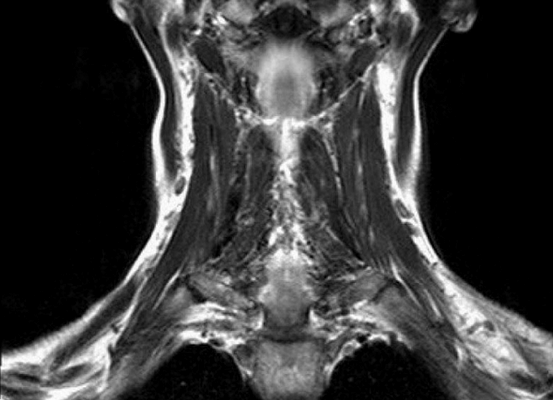

Результат МР-сканирования мягких тканей шеи

МРТ мягких тканей шеи назначают при наличии следующих симптомов:

дисфункция слюнных желез;

нарушения мозгового кровообращения;

признаки заболеваний щитовидной железы;

гипертония неясной этиологии и пр.

МРТ мягких тканей шеи